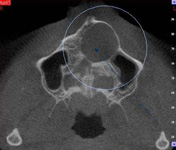

3D DVT - NewTom

Je speciální zubní digitální tříprostorový tomograf (3D), který umožňuje na základě jediného snímkování vytvořit všechny typy RTG zobrazení, které jsou pro lékaře potřebné. Díky používané technologii tzv. „kuželového paprsku“ a speciálním senzorům je výrazně zmenšená dávka záření - o více jak 80% proti klasickému CT vyšetření. To je významné zejména u dětí. Pomocí tohoto přístroje je možné zjisti skutečnou situaci v čelistních kostech pacienta tedy množství kosti - můžeme změřit skutečnou šířku i výšku kosti, i kvalitu kosti (hustotu) v místě uvažované implantace. 3D (tříprostorové) zobrazení umožňuje zvýšit prostorovou představu operatéra ještě před vlastní operací a zároveň pacientovi lépe objasnit a ukázat oblast plánovaného zavedení implantátu.

Pacient „neumí číst“ RTG snímky, ale díky 3D zobrazení vidí „svoji skutečnou čelist“ - např. jak je nízká či úzká, vidí průběh nervu nebo velikost čelistní dutiny, což mu umožní i pochopení nutnosti v některých případech provést pomocné zákroky ještě před vlastním zavedením implantátu (viz. kostní štěp, sinus lift, kostní granulát...).

Vyšetření pomocí tohoto přístroje používáme i ve stomatochirurgii (zlomeniny čelistí, zuby moudrosti, cysty, onemocnění čelistního kloubu), ortodoncii (retinované zuby, nadpočetné zuby), parodontologii atd.